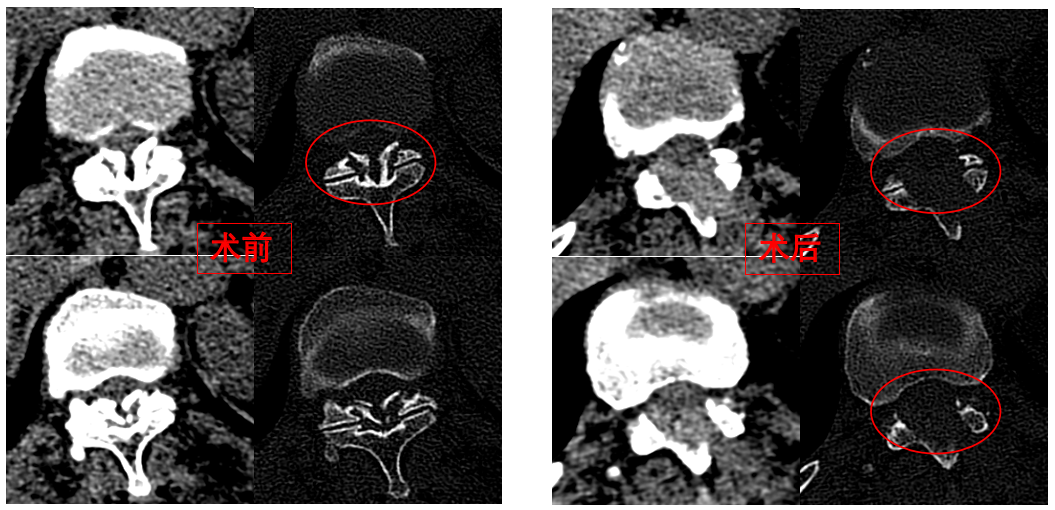

華西醫(yī)院成辦分院骨科副主任醫(yī)師張斌接診后,憑借豐富的脊柱治療經(jīng)驗,立即安排卓瑪阿媽做了系列精密檢查,檢查結(jié)果顯示,阿媽胸椎11/12節(jié)段黃韌帶嚴重骨化,導(dǎo)致椎管顯著狹窄,脊髓受壓,確診為嚴重的“胸椎黃韌帶骨化癥”,如果不及時手術(shù)最終可能面臨癱瘓的風(fēng)險。

手術(shù)歷時一個半小時,骨科脊柱微創(chuàng)團隊成功完整切除了壓迫脊髓的骨化黃韌帶,徹底解除了卓瑪阿媽的脊髓壓迫。手術(shù)過程順利,手術(shù)切口僅1厘米。

圖為卓瑪阿媽術(shù)前、術(shù)后胸椎CT照片對比。